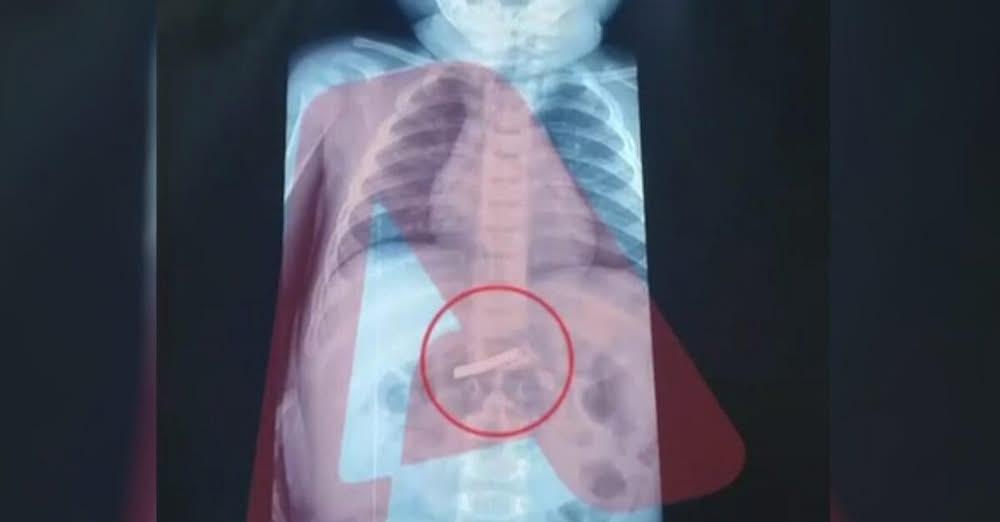

Ένας 3χρονος μεταφέρθηκε εσπευσμένα στο νοσοκομείο, το οποίο κατάπιε ένα ξυραφάκι. Το παιδί αφού έφτασε σε Παίδων της Αθήνας, υποβλήθηκε άμεσα σε ακτινογραφία, η οποία έδειξε ότι όντως υπήρχε το αιχμηρό αντικείμενο στο στομάχι του.

Όπως ενημέρωσαν οι γιατροί, τους γονείς του παιδιού, μετά την ακτινογραφία προσδιορίστηκε και το ακριβές σημείο όπου βρέθηκε το ξυραφάκι, ώστε οι χειρουργοί να προχωρήσουν σε επέμβαση αφαίρεσής του με ασφάλεια.